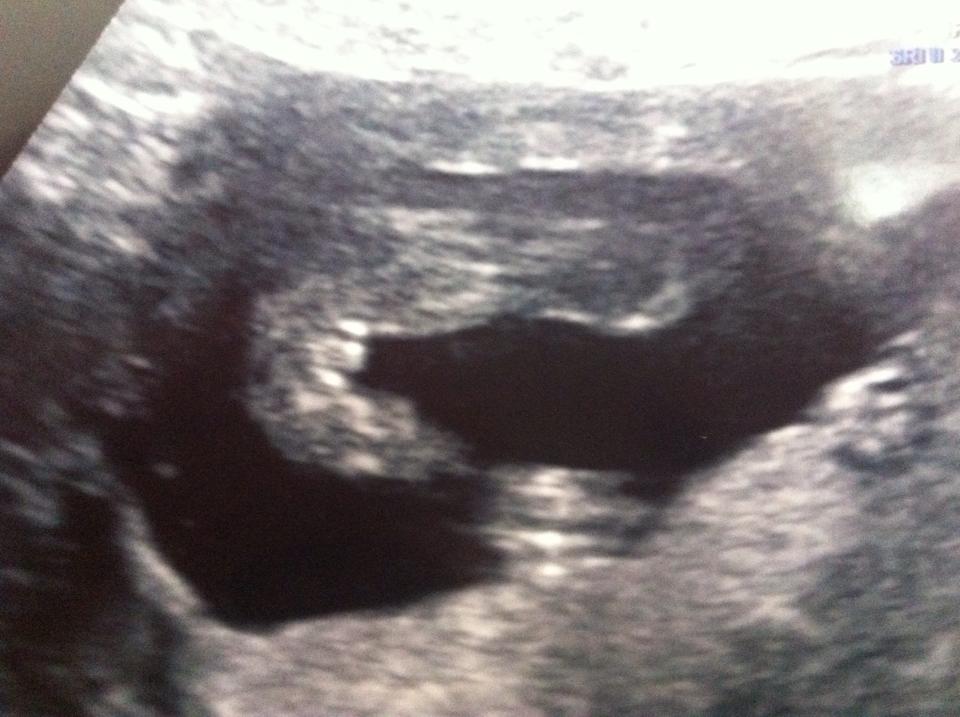

can you guys tell me what you think? thanks x Attachment 21507

Looks boyish but not super clear.

That image looks like a boy but could be labia too. Any others?

Looks boyish to me

does anyone agree with the sonographer and think the baby is a girl?

It could very well be a girl...sometimes it is hard to tell from just one picture :) Surely the sonographer saw something we do not since she is telling you girl.

hope so... but I feel so in shock it's a girl i wouldnt be surprised to find out its a boy at the 20 week scan! she did spend a lot of time looking and even pointed out all the girl parts during the scan and i actually thought this potty shot really looked like a girl lol! it's a rollercoaster this pregnancy!! :/

Well maybe the parts are just a little swollen. If you saw lots of girl parts and she was pointing them all out, I would be cautiously optimistic ...at least until your 20 week scan :) Good Luck!!